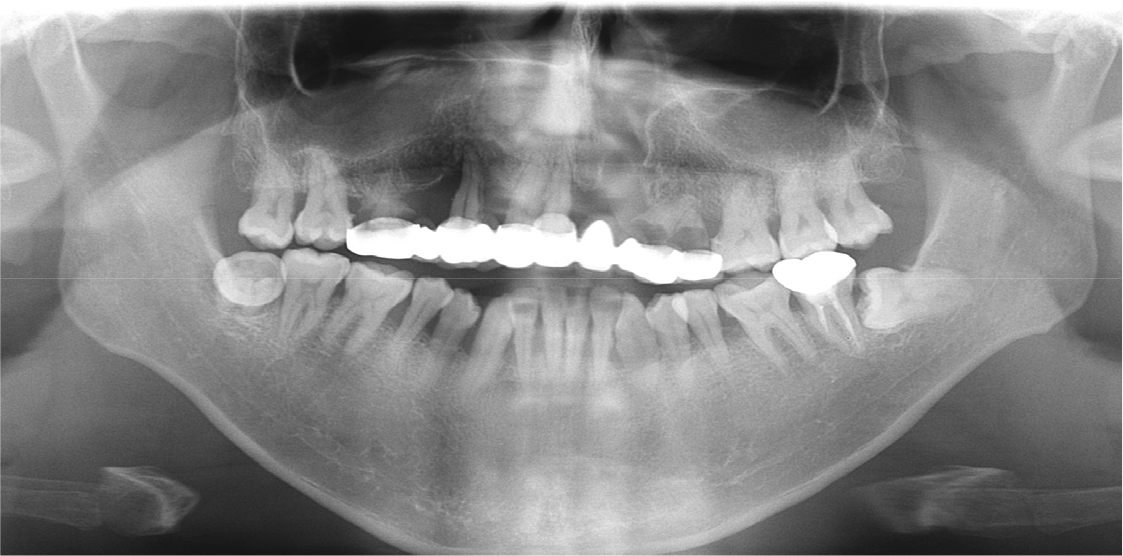

A 35-year-old man with left unilateral cleft lip and palate complained of pain in the maxillary right molar area. Approximately 25 years ago, the patient received treatment with a 10-unit fixed prosthesis with the maxillary right first molar, canine, and central and lateral incisors and maxillary left first and second premolars as the abutment teeth. The clinical and radiological examinations revealed residual roots of the maxillary right first molar and maxillary left first and second premolars due to severe caries. Moreover, severe alveolar bone loss was observed in the maxillary anterior area (Fig. 1). The maxillary right and left third molars were severely extruded because they had no opposing teeth. At maximum intercuspation, the bite was open, and there was occlusal interference between the molars on both sides due to eccentric movement of the jaw (Fig. 2).